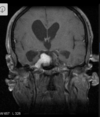

Q

A

Esclerose mesial temporal

Observe a perda de volume, que indica atrofia e causa aumento secundário do corno temporal do ventrículo lateral.

O sinal alto no hipocampo reflete a gliose.